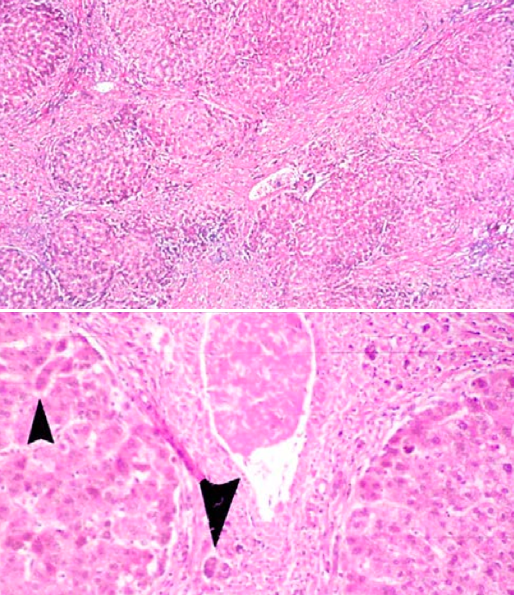

What would you expect to see on histologic analysis of this myocardium with multiple patchy white infiltrates from sarcoid?

Non-caseating granuloma: nodular multinucleate giant cells, epithelioid histiocytes w/pink cytoplasm and lymphocytes in the periphery.

What would you expect to see on biopsy of this hilar lymph node in a patient who had sarcoidosis?

Non-caseating granulomas with multinucleate giant cells and surrounding epitheliod histiocytes. You can also see asteroid body inclusions